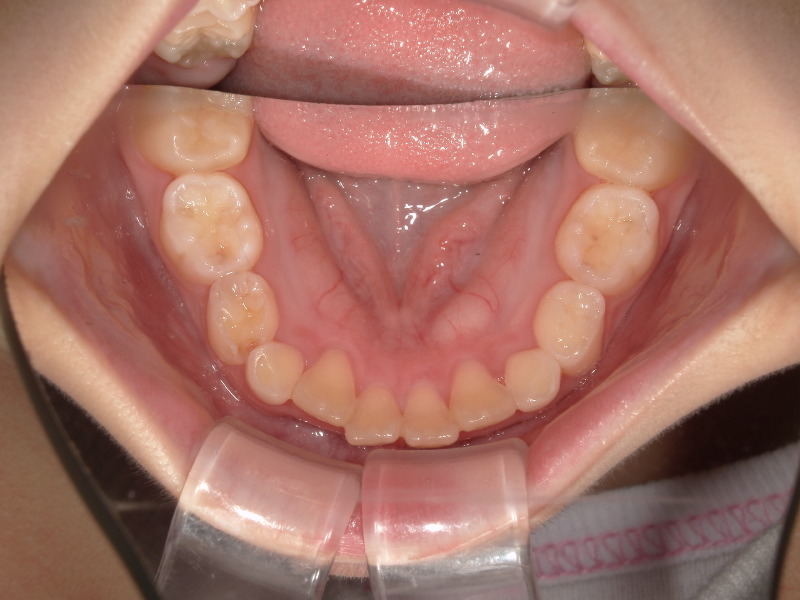

治療開始時

3ヶ月の経過

マウスピースとアクティビティーを3ヶ月続けた経過です。

入れなかった歯が少しずつ綺麗に並んでいいアーチになってきています。

マウスピースをいれて寝ると朝少し動いてるような痛みがあったそうです。

痛みがあるといってくれる子も少し、といった程度です。